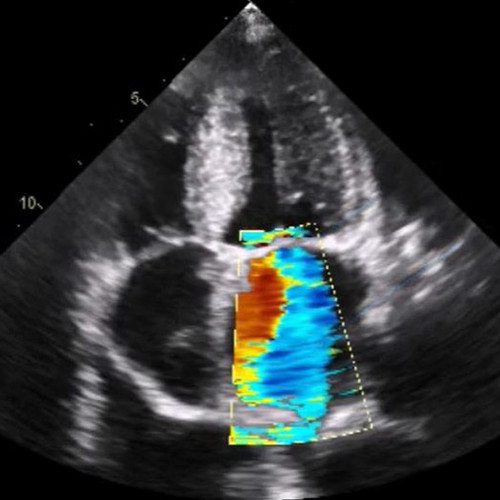

New Textbook Describes All Aspects of Focused Ultrasound - Focused。About Focused Ultrasound。Focused Cardiac Ultrasound Emergency Setting - Focus Ultrasound Exam。小動物のための超音波技術に関する専門的なガイドブック。- タイトル: Focused Ultrasound Techniques for the Small Animal Practitioner- 編集者: Gregory R. Lisciandro- 出版社: Wiley Blackwell- 目次: 基本的な超音波原理と技術、腹部FAST、腎臓、膀胱、脾臓、繁殖、胸部FASTなどの章を含む※写真のような、マーカー、書き込みと、表紙の痛みがあります。※定価がわかりませんが、他のサイトの出品ページを写真に載せておきます。ご覧いただきありがとうございます。#獣医学#小動物#超音波。Ultrasound: Clinical Techniques and Technical Advances。関節の構造と機能。生命医学倫理。日本精神神経学会 専門医認定試験問題 解答と解説 第1〜4集

• New Textbook Describes All Aspects of Focused Ultrasound - Focused

• About Focused Ultrasound

• Focused Cardiac Ultrasound Emergency Setting - Focus Ultrasound Exam

• Ultrasound: Clinical Techniques and Technical Advances